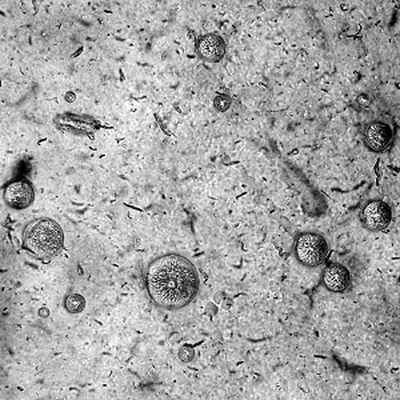

Морфология. Mycoplasma pneumoniae — мелкий анаэробный патоген, не имеющий клеточной стенки и паразитирующий в клетках дыхательной системы человека. Эти высоковирулентные штаммы по своему размеру сравнимы с вирусами. Бациллы присутствуют в грунте и подземных источниках, но полный жизненный цикл их проходит только в теле человека или животного. У людей микробы вызывают заболевания респираторного тракта — легочной микоплазмоз. Клетки микоплазм имеют грушевидную, гантелевидную, палочковидную, гранулярную или глобулярную форму с ветвящимся мицелием, а также микроворсинки и характерные терминальные структуры на одном полюсе. Бактерии требовательны к питательным веществам, но имеют полностью независимую метаболическую активность. Микоплазмы обитают внутри зараженных клеток и используют их энергию для осуществления собственного метаболизм. Они содержат РНК и ДНК, имеют отграничивающую мембрану, но лишены плотной клеточной стенки. Благодаря тому, что структура микоплазм схожа со строением нормальных клеток, микробы долгое время не распознаются иммунокомпетентными клетками и остаются резистентными к противомикробным средствам. Микоплазмы очень подвижны. Они свободно перемещаются от одной клетке к другой, непрерывно заражая их. Даже небольшое количество возбудителя в организме может вызвать патологический процесс. Это связано с высокой вирулентностью бактерий и их способностью крепко связываться с клетками организма.